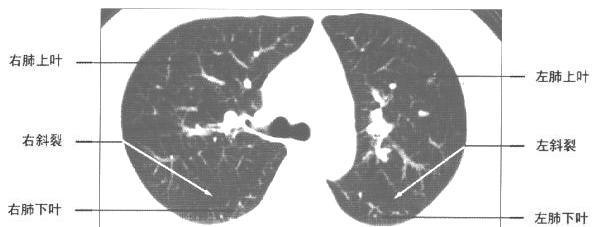

| 显示双侧斜裂层面

| 显示各肺叶层面